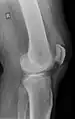

Quadriceps tendon rupture in plain X-ray

Quadriceps tendon rupture in plain X-ray: Incomplete rupture with haematoma in tendon.